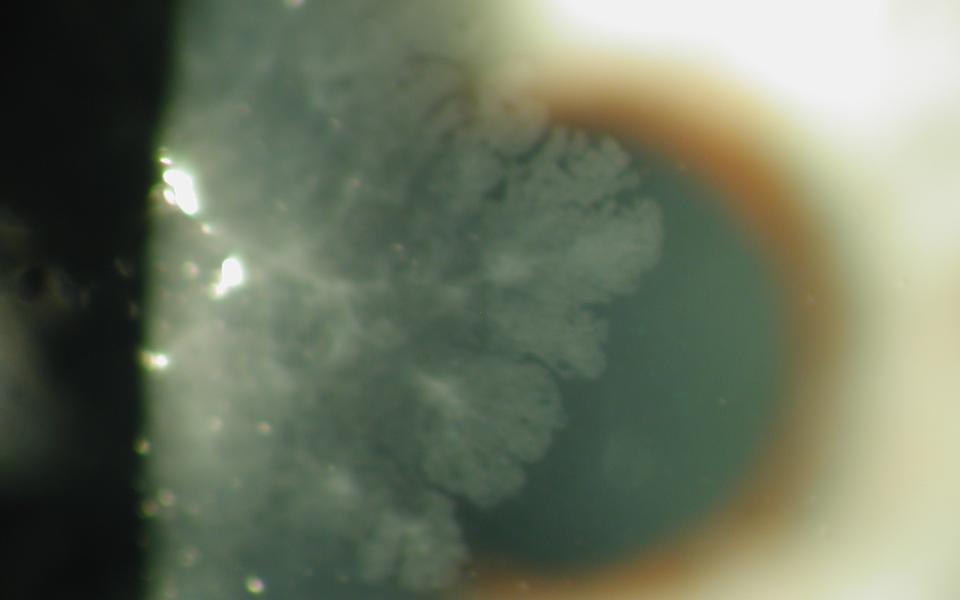

47yo female presented with unilateral reduction of vision in her right eye. Slit lamp examination revealed a anterior subcapsular cataract. The left eye showed early nuclear sclerosis only. On